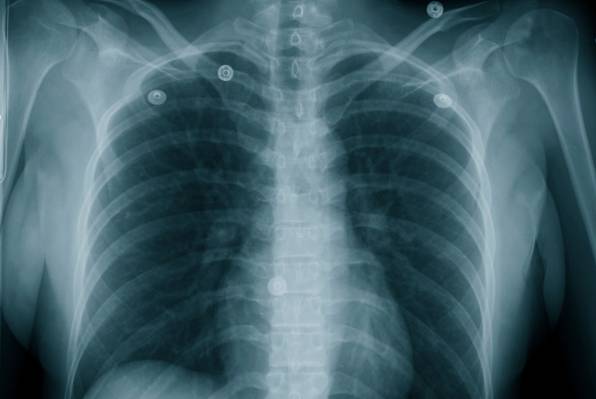

Ako se već ne možete odreći cigareta, bez obzira koliko znali o svim štetnim stranama koje ono sa sobom nosi, barem smanjite šansu od obolijevanja od raka. Postoje naime brojni načini kako pluća možete očistiti od katrana i smanjiti rizike od pojava infekcija.

Određene namirnice itekako mogu pomoći da malo pročistite pluća. Zapamtite da pluća ne možete u potpunosti očistiti samim konzumiranjem ovih namirnica, ali se barem u određenoj mjeri možete osloboditi toksina.